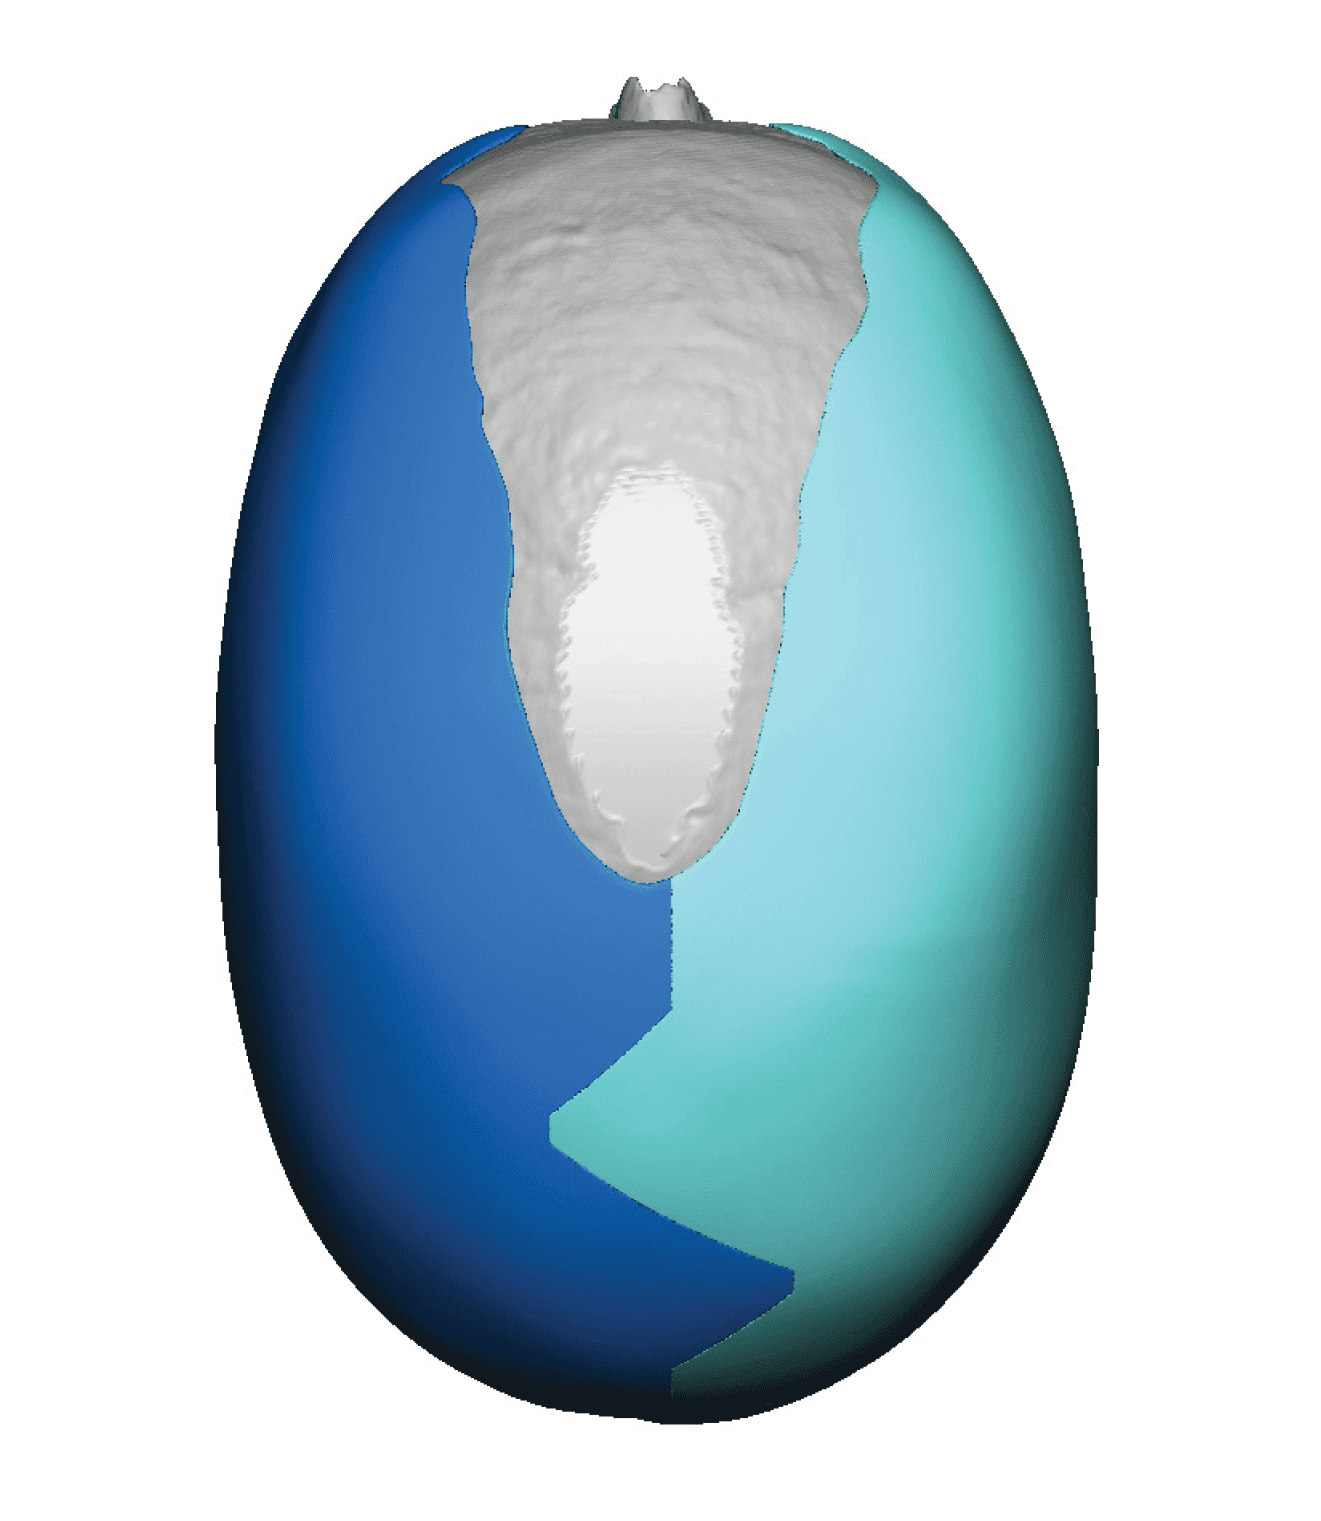

Severe narrowing skull deformity from prior sagittal craniosynostosis repair as an adult.

Complete replacement of entire skull by a custom implant with temporal fat injections.

Severe narrowing skull deformity from prior sagittal craniosynostosis repair as an adult.

Complete replacement of entire skull by a custom implant with temporal fat injections.